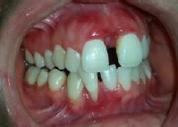

Lâexamen exobuccal Ă©tait sans particularitĂ©s. Lâexamen endobuccal a objectivĂ© une inflammation marginale modĂ©rĂ©e Ă sĂ©vĂšre gĂ©nĂ©ralisĂ©e avec un indice dâOleary Ă 68%, un indice gingival (BoP = Bleeding on Probing) Ă 76%, et un trama occlusal sur 42 (Figure 1). Le bilan parodontal montre des sites avec une profondeur de sondage (PS) de 12mm, et plus de 50% des dents prĂ©sentant une perte dâattache â„ 5mm. Le bilan radiographique a montrĂ© des pertes osseuses terminales, avec un rapport perte osseuse/Ăąge Ă 4,5 (Figure 1)

Le diagnostic de parodontite stade IV grade C généralisé a été proposé (1), avec un pronostic irrationnel au traitement pour les dents 25, 36, 42 et défavorable pour 11, 21, 35, 46 (2).

La thĂ©rapeutique Ă©tiologique a consistĂ© en une Ă©ducation Ă lâhygiĂšne bucco-dentaire, une Ă©limination des facteurs de rĂ©tention de plaque, lâextraction 42+rĂ©section radiculaire et rĂ©alisation dâune contention en fibre de verre avec la couronne ; dâune instrumentation non chirurgicale supra et sous gingivale

par quadrant (3) combinĂ©e Ă une antibiothĂ©rapie (3,4). Une chirurgie avec lambeau dâaccĂšs selon la technique du lambeau avec incision intrasulculaire (open flap) a Ă©tĂ© rĂ©alisĂ©e sur la 46. Une thĂ©rapie parodontale de soutien associĂ©e Ă une phase correctrice a Ă©tĂ© mise en place aprĂšs la thĂ©rapie parodontale active (5). La rĂ©habilitation orale a consistĂ© dans un premier temps Ă rĂ©aliser une correction orthodontique (Figure 2) ; et dans un second temps la conception dâune Ă©pithĂšse gingivale (Figure 3)

AprĂšs 6 mois, pas de profondeurs de poches â„ 6mm, avec un indice de plaque Ă 9% et un indice gingival < 10%. La thĂ©rapeutique non chirurgicale a permis un gain dâattache

stable qui sâest traduit par une diminution des profondeurs de sondage en regard de la 11, 21, et 36 dont le pronostic Ă©tait dĂ©favorable, mais aussi lâapparition dâimportantes rĂ©cessions postthĂ©rapeutique (Figure 4). La chirurgie avec lambeau dâaccĂšs a permis Ă©galement dâamĂ©liorer le niveau osseux de la 46. Le pronostic gĂ©nĂ©ral Ă long terme de la patiente a Ă©tĂ© amĂ©liorĂ©.

Figure 4 : (a) Vue clinique Ă 6 mois ; (b) bilan radiographique Ă 3mois (b) ; (c) Retro alvĂ©olaire sur la 46 avant et aprĂšs lambeau dâassainissement